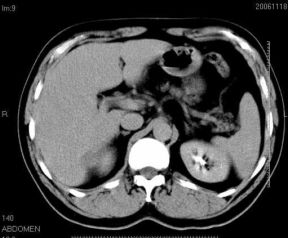

男性,48岁

肝内占位,性质?

肝内多发低密度占位病变,边缘清晰,无强化,肝转移瘤可能

肝内多发低密度占位病变,边缘清晰,无强化,肝转移瘤可能大,请将胃喝水充盈以后再扫描看看,我看大弯侧胃壁较厚。

肝内多发不规则形状低密度灶,强化不明显,考虑转移,积极查找原发灶

患者,男性,48岁

肝内多发低密度类圆形病灶,边缘清晰.增强无强化.

意见:1,考虑多发转移瘤;

2,囊肿与血管瘤不排除.

肝内多发不规则形状低密度灶,强化不明显,考虑转移,找找原发灶

1肝内多发低密度影,考虑:转移瘤 2胃大弯侧胃壁明显增厚,建议胃镜检查除外胃癌

我认为先考虑原发性肝癌。

首先考虑转移瘤。

多考虑转移瘤

转移瘤?